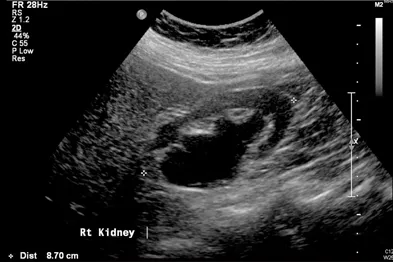

- USG KUB: First-line in pregnancy & children. Detects hydronephrosis, stones.

- ↑ Pressure → hydroureter/hydronephrosis.

- Diagnosis: Ultrasound (hydronephrosis), CT (level/cause), RFTs.